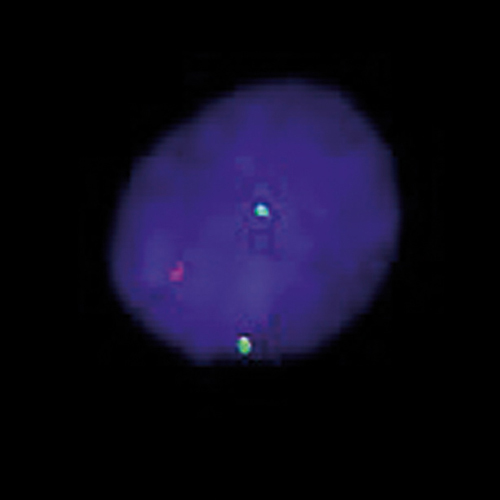

The translocation t(8;14)(q24;q32) is the characteristic chromosomal aberration of Burkitt's-type of lymphomas. This translocation fuses the MYC gene at 8q24 next to the IGH locus at 14q32, resulting in overexpression of the transcription factor MYC. Detection of the t(8;14) is aimed to help in the diagnostic process of patients with high-grade B-cell lymphomas because treatment strategies differ between Burkitt and other high-grade lymphomas. The MYC/IGH t(8;14)(q24;q32) specific FISH probe is optimized to detect the reciprocal translocation t(8;14) in a dual-color, dual-fusion assay.